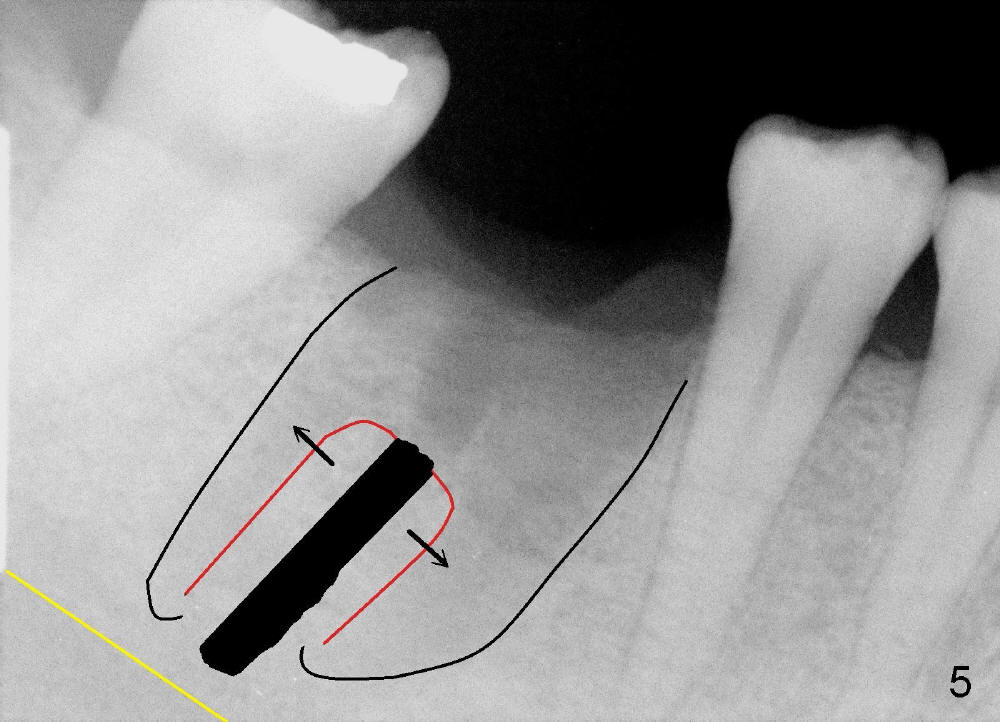

A 43-year-old lady had the lower right first molar extracted in other office last month. The socket appears to be healing normally (Fig.1). Tatum tapered implant 6x17 mm is planned (Fig.2). The implant is to be placed inside the septum (Fig.3 red outline; black: mesial and distal sockets; yellow: the upper border of the inferior alveolar canal). Either 1.5 mm pilot drill or 2 mm RT is used to start osteotomy in the septum at the depth of 17 mm (Fig.4 white outline). The osteotomy is enlarged with alternating use of osteotomes and 17 mm series tapered drills or Bicon reamers if autogenous bone will be needed (Fig.5 black), while the septal bone is pushed mesiodistally (arrows). After application of taps, an appropriately sized implant is placed (Fig.6 white). The septal bone continues expanding (arrows), whereas the mesial and distal sockets are being decreased.